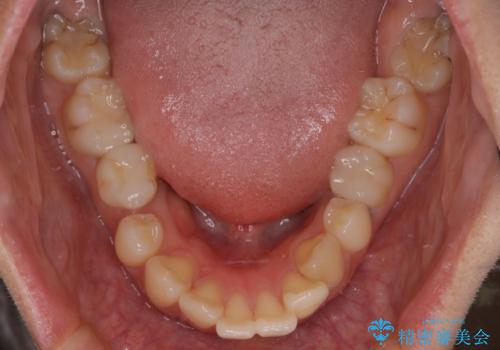

- 口元が出ていること(突出感)を気にされ、これを下げたいという主訴でご来院されました。精密な検査の結果、前歯を大きく後退させ、口元を改善するためには、スペースの確保が不可欠と診断しました。そこで、上下左右の第一小臼歯(4番目の歯)を計4本抜歯し、そのスペースを利用して前歯全体を奥へ移動させる抜歯矯正の治療計画を立案。確実な歯の移動を実現するため、ワイヤー矯正装置を使用しました。

今回の矯正治療では、口元の突出感を解消するためのスペースを確保するため、計画通り上下左右4本の小臼歯を抜歯しました。装置には、確実な歯の移動と細やかな調整が可能なワイヤー矯正を採用。抜歯によってできたスペースを最大限に利用し、前歯を奥へ、そして垂直的に慎重に移動させました。